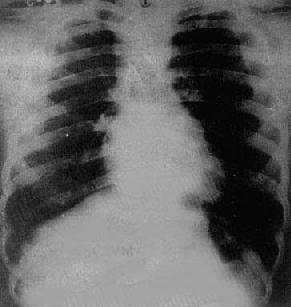

图3-2-18 心包积液(后前位)

心影向两侧普遍增大,心缘正常弧度消失,

上腔静脉增宽,主动脉影缩短,肺纹理减少